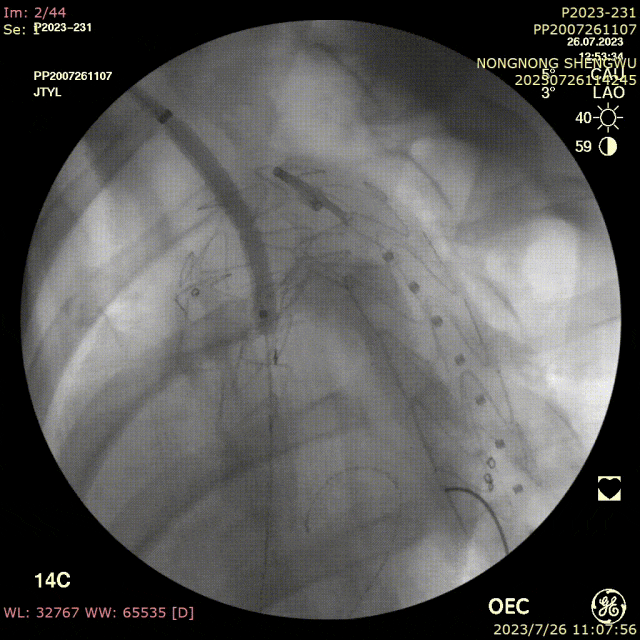

手术过程:

全麻下双上肢穿刺,右股动脉切开,左上肢路径造影,右上肢进保护性导丝,对支架预开窗后植入升主,因破口较大,支架近端掉入破口,远端扭转遮蔽左颈总动脉及头臂干,窗口对破口,再次植入一枚38-80支架,封住近端破口后,以8*60支架开放右侧头臂干,6*10人工血管行右锁骨下-左颈总搭桥,取颈前静脉行左椎动脉-人工血管搭桥,之后造影,头臂动脉均通常,术后约2小时患者清醒。